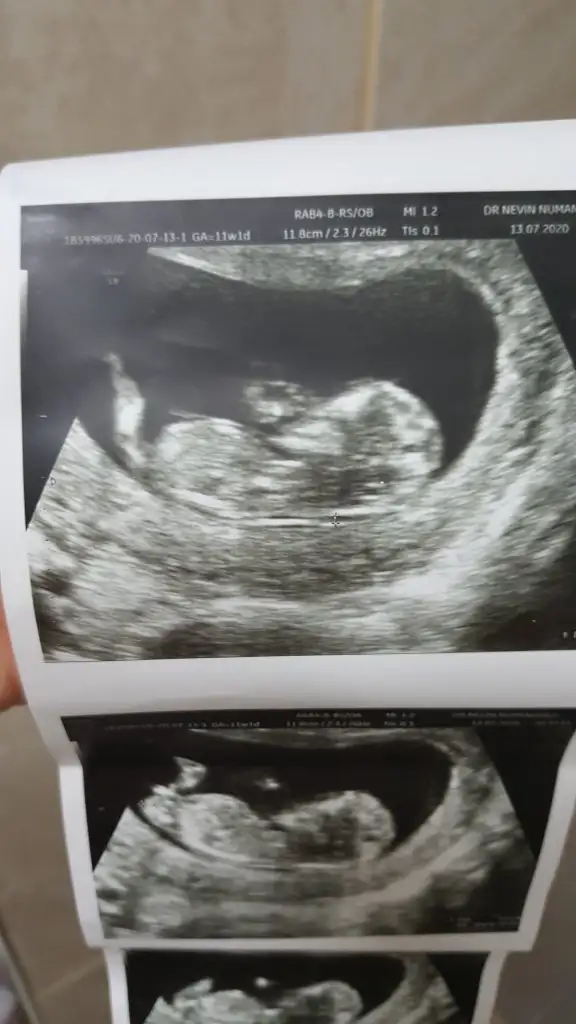

Erkek görünüyorBunu gece yükleyememiştim bacakları havada fotosu,mesajı nasıl düzenleyeceğimi bilemediğim için tekrar cevapla yaptım kusura bakmayın![]()

12+6 haftaKaç haftalık sanki erkek gibi geldi başka usg varsa paylaşın az yan pozisyonda minnoş![]()

Dr bir tek bunu verdi maalesef teşekkürler cvp içinKaç haftalık sanki erkek gibi geldi başka usg varsa paylaşın az yan pozisyonda minnoş![]()

Şimdilik kız yönünde 12 haftayıda paylaşın12 de tekrar gidicem o zamanda atarım merakıma yenildim![]()